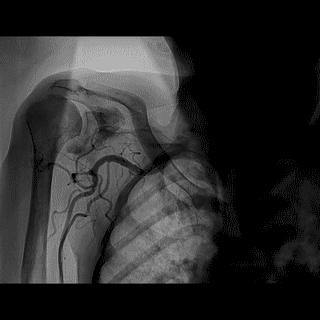

操作:升主动脉造影,寻找静脉桥血管

➢ CASE 3

AL1.0

升主动脉造影未见桥血管显影,原位血管造影也没发现竞争血流迹象,可以确定桥血管已闭塞,必要时可以借助冠脉CTA辅助诊断